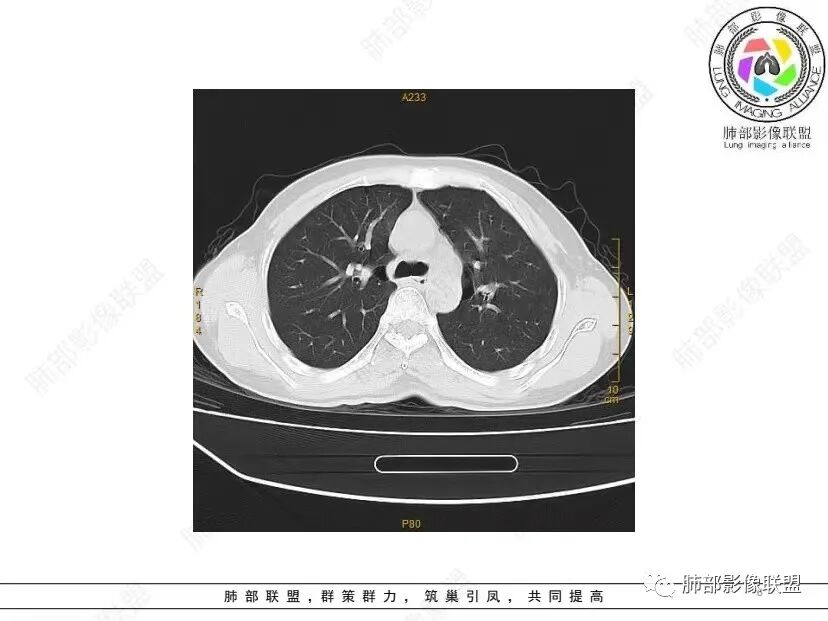

中年女性,否认肿瘤病史,双肺多发气囊,中下肺相对多发,考虑LIP,鉴别BHD综合征。

秦化君: 晨读 双肺不均匀散在多发囊状影,大小不等,部分囊形态欠规整,壁薄均匀,部分囊胸膜下平行。双肺少许斑片状磨玻璃影,边缘模糊。考虑BHD综合征。鉴别PCP,LIP。

红日初升: 中年女性,双肺多发气囊,背景干净,大小不一,下肺韧带旁较大,考虑BHD,鉴别LIP、LAM

玫: 晨读:女,49岁,双肺散在多发囊性病灶影,薄壁,部分层面病灶形态欠规整,右肺下叶少许磨玻璃影,边缘模糊,考虑LIP,鉴别BHD。

宇宙: 中年女性,两肺多发大小不等薄壁囊状影,两肺纵膈胸膜下分布明显,考虑BHD,鉴别LAM

放射线 (王秀仙): 双肺多发囊状影,大小不等,部分囊壁呈磨玻璃样,另双肺见斑片状磨玻璃影,边缘模糊。女性,考虑LIP,鉴别BHD

段建民: 双肺多发囊状影,多成圆形或三角形,囊壁薄且均匀,正常肺野内透过度尚可。双肺多发囊状影的鉴别,中心肺气肿,间隔旁肺气肿,PJP,支气管扩张,囊肿,支气管肺发育异常;LAM LIP PLCH BHD;囊腔腺癌,转移瘤,血播金葡菌……

本病例首先考虑BHD。

小飞: 晨读,中年女性,病史保密,两肺散在薄壁囊腔,肺底较多,部分较大,双肺少许磨玻璃密度影,考虑LIP

良孑: 两肺多发含气囊腔,大小不等,囊周见血管伴行,首选BHD,建议查双肾情况,鉴别Lam

这个病例目前影像特点,多囊,囊主要位于下肺,胸膜下及小叶核心为主

伴随少许索条,而且这些病灶与囊不一定有相关性

囊的分布,PLCH基本可以排除

囊壁薄且均匀,光滑,形态规则,基本除外恶性

单纯囊,无斑片及其他实性病灶,感染不支持,可能的是:LAM、BHD、LIP

从囊的分布、大小,BHD可能性可能大一些,但是LIP、LAM都可以这样表现,具体诊断应该是这三种之一,影像缩小到这里我觉得就差不多了,结合临床考虑就行,不支持靠影像强下结论。